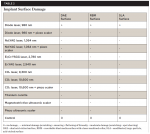

After visual assessment, the specimens were evaluated by scanning electron microscopy (SEM) for the presence of residual cement and for damage to the titanium surface (Table 2).

From a visual standpoint, none of the treatments was completely successful at removing all of the cement from the implant surfaces (Table 1). The SEM images supported the visual observations with respect to effectiveness of cement removal and expanded on these findings from the perspective of surface alterations.

The Ti curet, magnetostrictive scaler, piezo scaler, Nd:YAG + piezo scaler, and the CO2 10,600 nm + piezo scaler showed moderate to mostly effective treatment results, although scratches on the implant surfaces were observable. A flattening and smearing of the crests of the implant threads was apparent under SEM (Figure 4, Figure 5, Figure 8, and Figure 9). These effects were not evident when the two lasers were applied as a monotherapy.

Damage to the cement layer and implant surfaces was visually apparent between the threads of the implants treated with the diode laser (Figure 10 and Figure 12). Additionally, SEM revealed areas of heat-induced titanium surface melting and cavitational defects with melting of residual cement (Figure 11 and Figure 13). SEM examination of implants subjected to the diode + piezo scaler protocol showed chipping, smearing, and flattening of the implant threads.

The post-treatment SEM images revealed that surface damage varied and included scratching, flattening, smearing, and chipping of the crests of the implant threads. Additionally, both visually and under SEM, the diode laser, when used as a monotherapy, showed localized areas of carbonization and cement surface damage due to excessive heat.When used as a dual therapy with the piezo scaler, less damage was evident as the diode laser was not used alone for the total decontamination time. Although the damages noted might preclude osseointegration or soft-tissue adherence at specific sites on an implant, extensive damage that might interfere with re-osseointegration of an entire implant surface was not observed using any of the test instruments at the prescribed settings (Table 2).

Surface scratching, smearing, and flattening of the crest of the implant threads were common findings using SEM, with localized areas of surface melting evident after the use the diode laser. While not substantial enough to preclude integration of an entire implant, whether these surface changes or corrosion from the shedding of titanium particles are sufficient to cause an adverse tissue reaction is unknown.